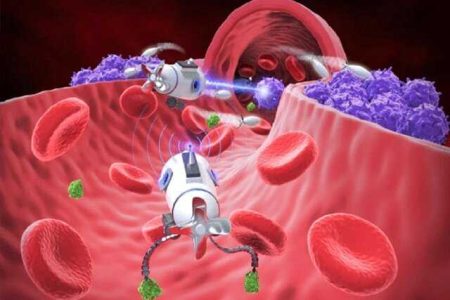

رونمایی از کوچک ترین بمب افکن دنیا !

به گزارش گیلی نت، محققان دانشگاه آلاباما با همکاری پژوهشگرانی از موسسه تحقیقاتی سنت پاو وسیبربن، ماده ای در مقیاس…